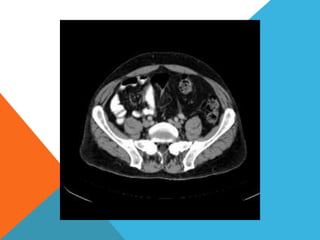

El paciente presentó síntomas de sangrado digestivo y pérdida de peso. Exámenes revelaron gastritis crónica asociada a H. pylori. Un tumor fue descubierto en una colonoscopia normal. La cirugía removió un tumor fibroide solitario, una rara neoplasia mesenquimal que usualmente crece lento y tiene bajo potencial de malignidad. El pronóstico después de la remoción quirúrgica es generalmente bueno.